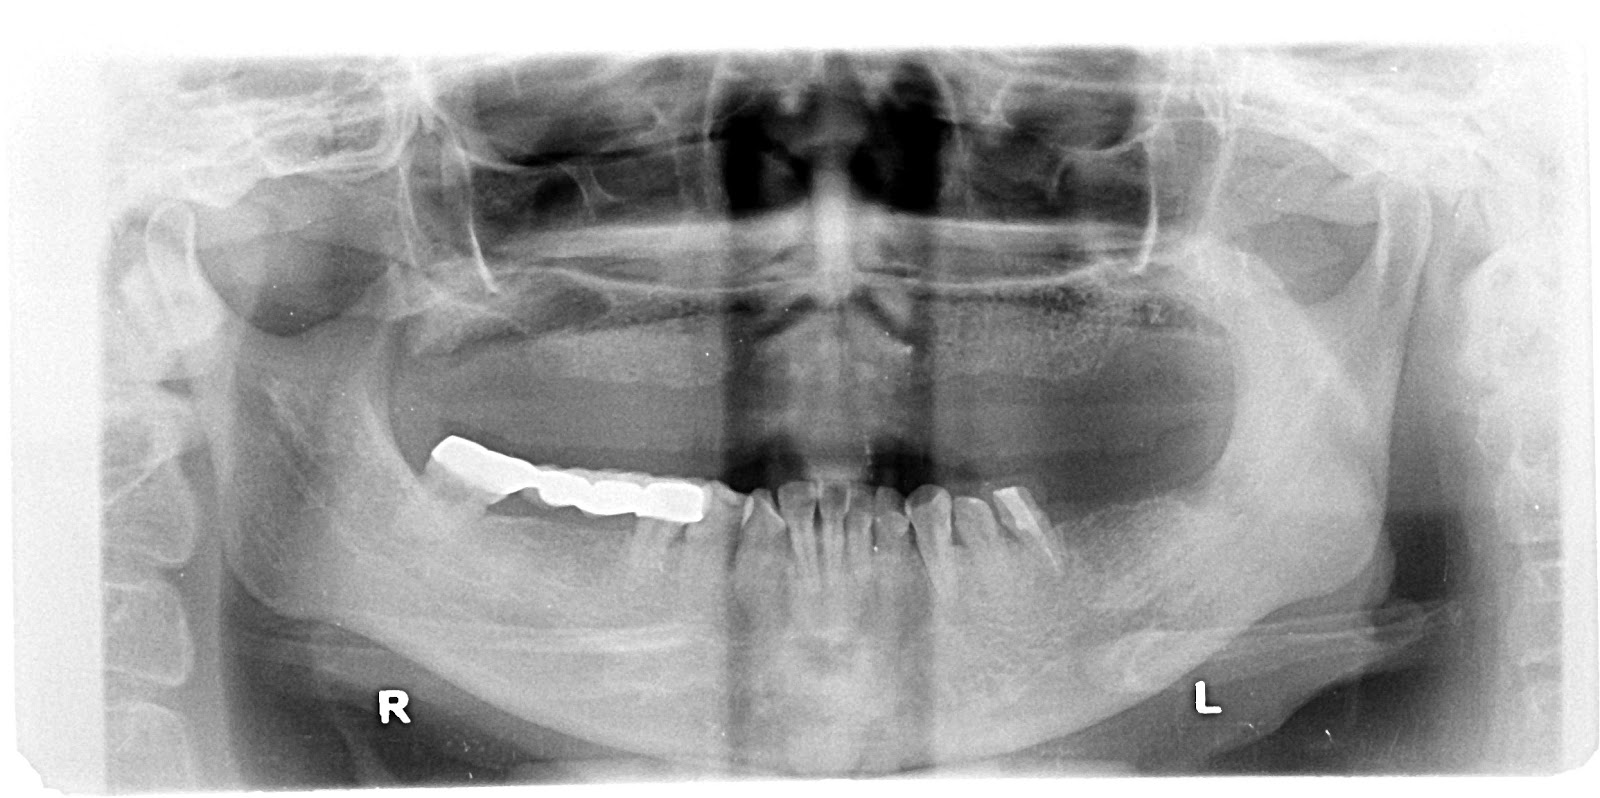

Full arch dental implantations via digital surgical guide and bone grafting via VISTA technique

PreOP

Post implant Panoramic X-ray